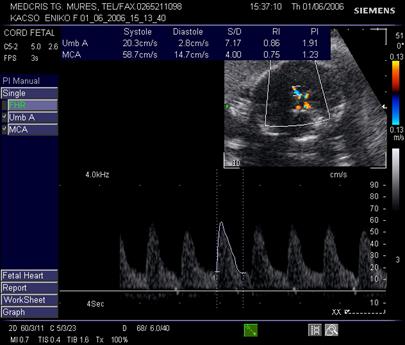

Doppler in circulatia cerebrala

Creierul fetal primeste circa 40% din debitul cardiac total. Cele 3 scurtcircuite ale aparatului fetal cardio-vascular: canalul arterial, ductul venos si foramen ovale, permit devierea sangelui bine oxigenat spre creier, cord si suprarenale, in caz de hipoxie (teritorii privilegiate).

Daca cresterea tensiunii arteriale si a frecventei cardiace din cadrul hipoxiei fetale, sunt consumatoare mari de oxigen si autolimitate, redistribuirea fluxului de sange se face prin vasodilatatie compensatorie in "teritoriile privilegiate."

Poligonul Willis, sediul anastomozelor vasculare din principalele vase cerebrale, se identifica plecand de la sectiunea transversala a masurarii diametrului biparietal, prin baleierea sondei spre sectiunea bazei craniului.

Artera cerebrala medie are directia inainte si in afara, primeste sange din carotide si arterele vertebrale. Planul de reperare este cel al pedunculilor cerebrali, lateral de poligonul Willis. Ea reprezinta sediul preferat pentru velocimetria cerebrala.

In sarcina normala, rezistenta crescuta cerebrala se traduce in velocimetria cerebrala prin diastola scazuta. Aspectul normal al velocimetriei cerebrale permite aprecierea unei stari de bine fetale pentru 2 saptamani [17].

In cazul unei patologii gestationale (HTA, RCIU) repetarea examenului se va face la 2 saptamani, iar pentru valori anormale la 24 - 72 ore.

Velocimetria cerebrala , singura, nu aduce informatii asupra hipoxiei din circulatie.

Indicele Arbeille (raport cerebro-placentar) = IR a. cerebrala medie/IR a. ombilicala este supraunitar in conditii de sarcina fiziologica.

In afara fenomenelor de redistribuire a fluxurilor vasculare fetale, amplitudinea vitezelor diastolice la arterele cerebrale ramane inferioara fata de artera ombilicala, deci valoarea indicelui cerebroplacentar este supraunitara. Vasodilatatia cerebrala din redistribuirea fluxurilor sanguine, din suferinta fetala cronica, va determina o scadere semnificativa a IR cerebrala, cu trecerea indicelui cerebroplacentar in valoare subunitara.

Fig. nr.325. Doppler normal pe a. cerebrala medie , la 27 sapt.

Fig. nr. 326. Doppler pe artera cerebrala medie cu diastola crescuta si inversarea indicilor de rezistenta ( indicele Arbeille subunitar ) la fat de 34 sapt cu retard major de crestere intrauterina si sdr genetic